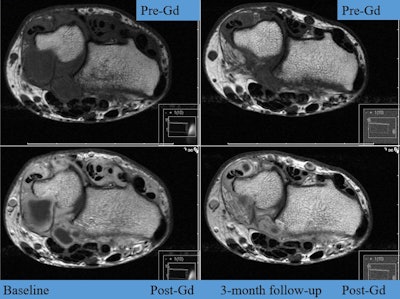

MR images of the wrist at baseline and three-month follow-up, pre- and postgadolinium (Gd), show reduction of synovitis and tenosynovitis. Images are from Diakonhjemmet Hospital and not an actual patient in ARCTIC. Images courtesy of Dr. Espen Haavardsholm.Nix ultrasound

The researchers found no statistically significant baseline differences between the two treatment groups in either of the combined MRI scores. The mean combined MRI inflammation score decreased during the first year in the ultrasound group by 64.2 and in the conventional strategy group by 59.4. These scores were maintained at the same level throughout the second year of follow-up.

There was no significant difference in change from baseline between the two groups at any time. The mean combined MRI damage score showed a small increase over time, with no significant difference between the two groups. In the ultrasound group, 39% of patients had MRI erosive progression compared with 33% in the conventional strategy group.